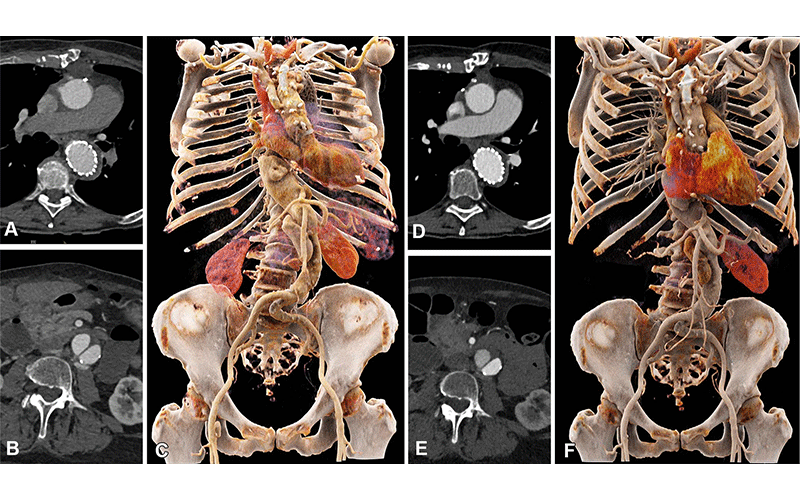

Comparison of image quality between EID CT with standard contrast media protocol and PCD CT with low-volume contrast media protocol using a matched radiation dose. Transverse and three-dimensional cinematic rendered images from thoracoabdominal CTA in a 71-year-old woman in group 2 are shown. (A–C) Images from third-generation EID CT with automated tube voltage selection of 90 kVp. (D–F) Images from PCD CT with reduced contrast media volume of 52.5 mL and VMI at 50 keV. Time interval between scans was 6 months. CTA = CT angiography, EID = energy-integrating detector, PCD = photon-counting detector, VMI = virtual monoenergetic images.